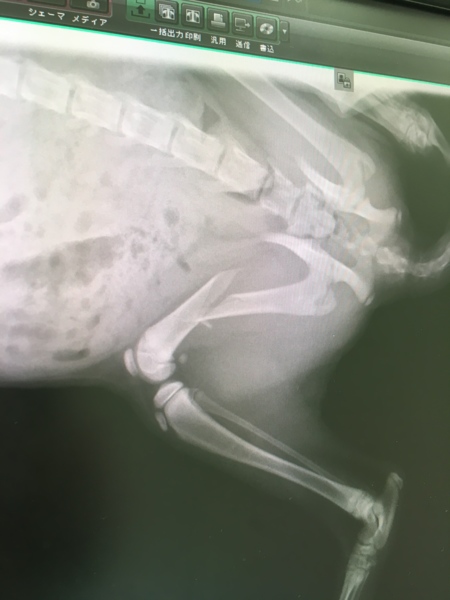

ルーシー骨折!

ルーシーさん骨折。目黒動物病院さんから小滝橋動物病院 目白通り高度医療センターにて手術。

5/18の夜発覚、5/19に初見病院に朝イチ診察、5/20上記病院に入院、5/21手術、5/28退院予定。